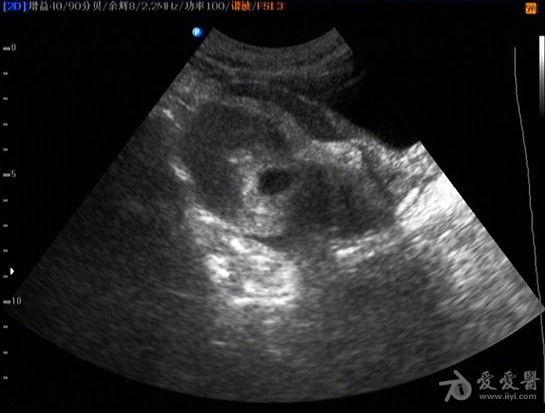

子宫穿孔超声表现图

子宫穿孔超声表现图,子宫穿孔超声图片

超声典型病例子宫穿孔

超声诊断子宫穿孔并大网膜嵌顿1例

子宫穿孔超声图片

子宫穿孔彩超下表现

子宫穿孔彩超图

子宫穿孔b超图片